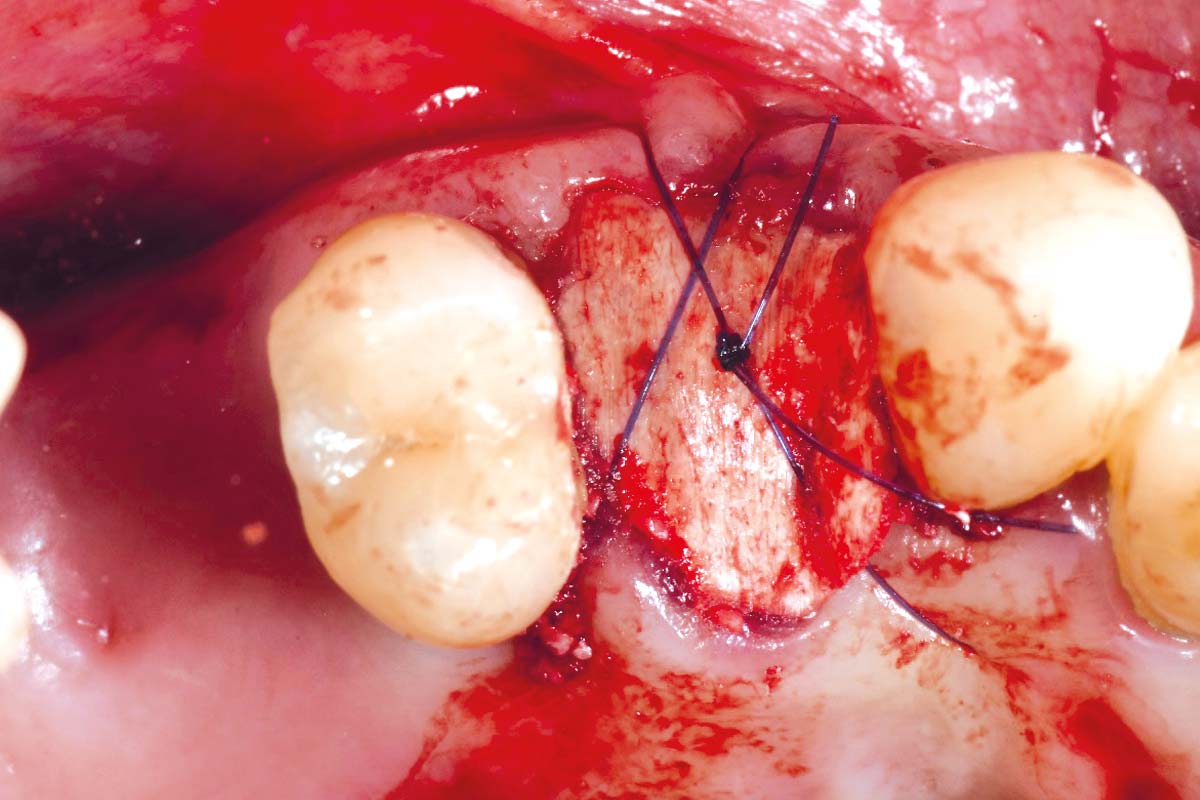

At the six-month re-entry, insufficient regeneration of the buccal plate was observed, compromising the available bone volume for implant placement. To address this deficiency, NOVAMag® SHIELD was introduced to reconstruct the buccal plate. Thus, an implant was placed followed by a membrane placement between the periosteum and the remaining buccal bone without fixation. Additional bone augmentation was performed to facilitate guided bone regeneration.